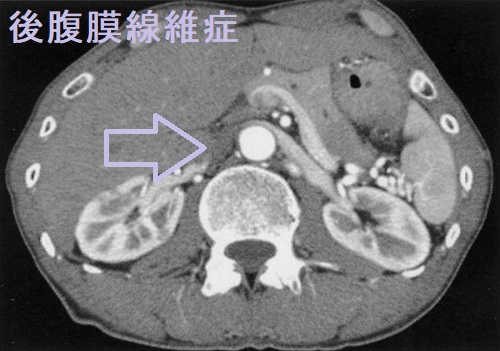

後腹膜線維症では、内臓を包む腹膜の背中側がガチガチに線維化します。腎臓から出て膀胱へ至る尿管を巻き込むため、尿の通過障害が起こります。結果、尿が腎臓へ逆流して、水腎症や急性腎盂腎炎を発症します。[Nephrol Dial Transplant. 2021 Sep 27;36(10):1773-1781.]

CT・MRIでは大動脈周囲に軟部影を認め、炎症性動脈瘤のような所見です。

IgG4 関連疾患との合併から、特発性後腹膜線維症の相当数がIgG4 関連後腹膜線維症とされます。(Intern Emerg Med. 2017 Apr;12(3):287-299.)